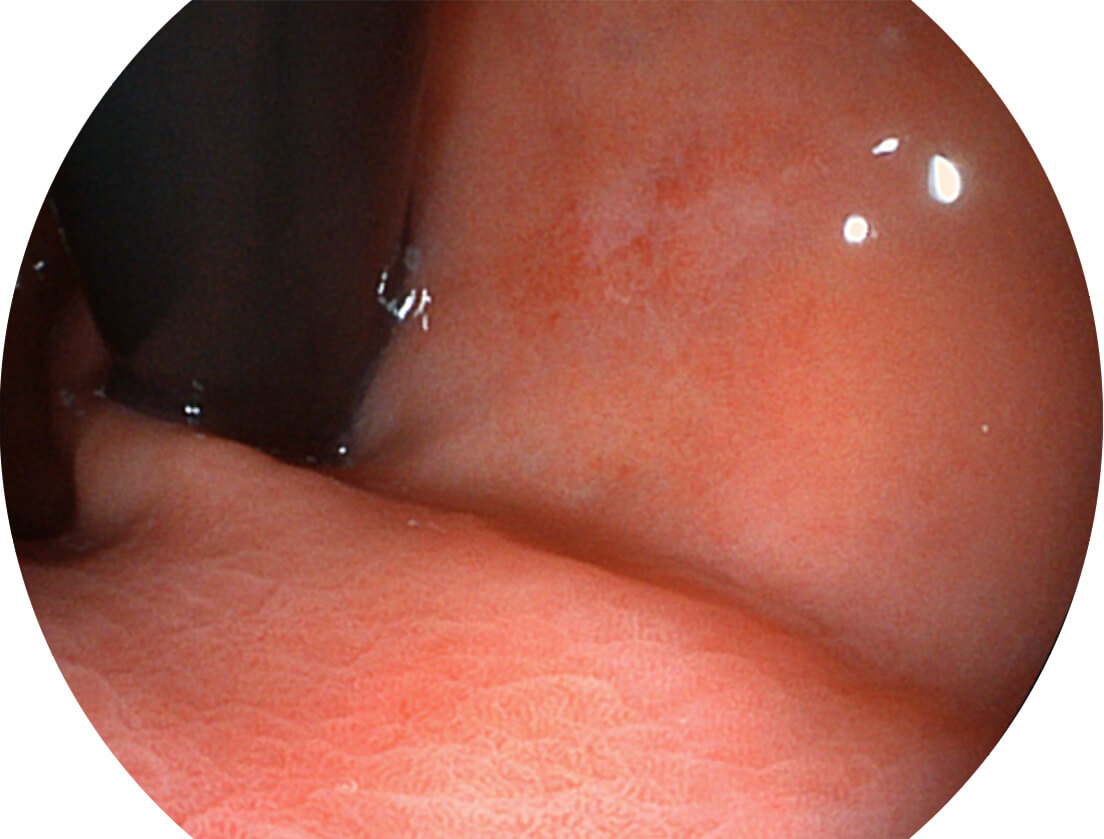

• 白光图像 SFI图像

图像具有高亮度、高黏膜血管颜色对比度的特点,且不改变粘液、食物残渣、粪便的基本颜色,可在中远景下进行观察,助力消化道早期疾病的诊断。